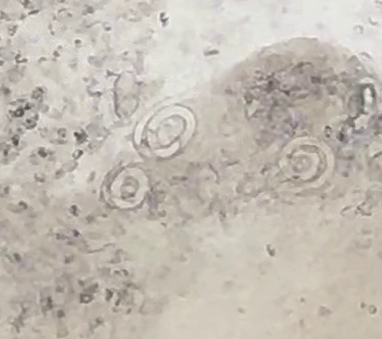

今回の感染した犬は体重17kgの中型犬です。お住まいは新青梅街道の北側、狭山湖よりとなります。目ヤニがで始めたとこのことで来院されましたが、眼検査と目ヤニの検査で東洋眼虫が確認されました。後日全身麻酔下で眼球洗浄、左右眼球から合計14匹の眼虫を取り除きました。

この後に、目ヤニの顕微鏡画像、麻酔下の眼虫摘出動画、摘出後の眼虫画像を掲載します。苦手な方はご注意ください。